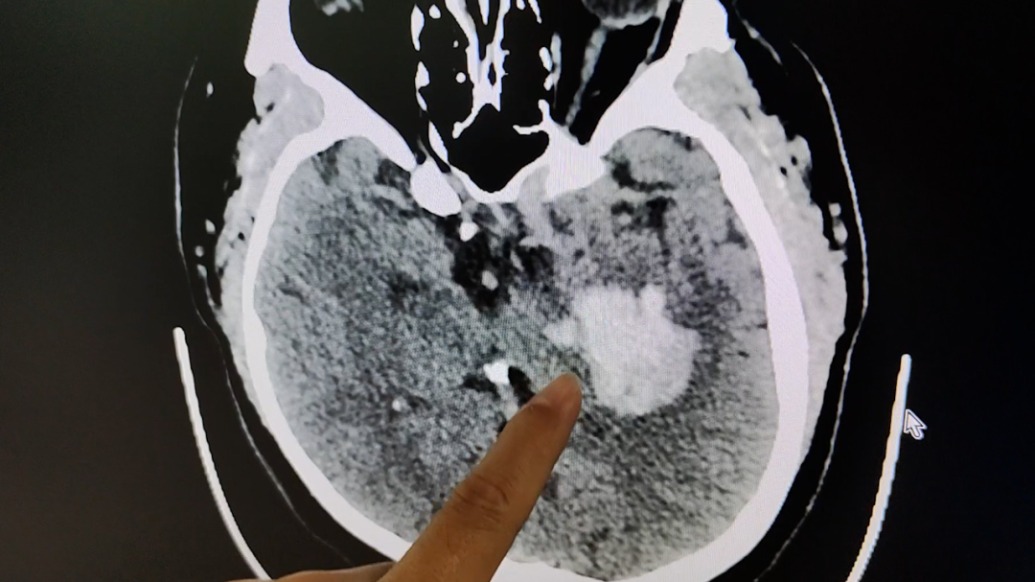

250斤小伙熬夜打游戲后突發腦出血

近日,廣東深圳。26歲的小丁打游戲至凌晨突發身體不適,送醫確診腦出血。小丁的母親稱他1.78米,250斤,愛擼串、喝啤酒、熬夜打游戲。術后,小丁正進行康復訓練。